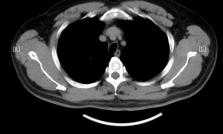

入院后急查血常规:白细胞总数4.35 × 106、淋巴细胞比率13.8%;细菌感染血清标志物检测:白细胞介素−6 53.2 pg/mL;C反应蛋白170.55 mg/L;血气分析(未吸氧状态下):PH 7.46,氧分压(PO2) 59 mmHg,二氧化碳分压(PCO2) 33 mmHg;尿、粪常规及肝、肾功能检查无明显异常;呼吸道九项、风湿系列、自身抗体、流感及支原体检查、新型冠状病毒感染检测等均阴性。痰涂片检见少量G−杆菌及G+链球菌;痰培养检测见正常菌群,结核耐药菌基因检测阴性;胸部CT平扫示:右侧胸膜局部增厚、粘连;右肺上、下叶所见考虑间质性改变并感染性病变(图2(A))。

入院第十日病情较前明显好转,复查胸部CT平扫示:右肺上、下叶间质性改变并少许感染性病变,较前(2023-09-28)吸收减少,右侧胸膜局部增厚,较前(2023-09-28)减轻(见图2(B)),患者遂出院。

出院后半年(2024年4月3日)复诊,一般情况良好,无咳嗽咳痰,复查胸部CT + 薄层示:1) 双肺上叶局限性肺气肿;2) 右肺下叶少许渗出,较前(2023-10-5)变化不显著,原右肺上叶感染已吸收;3) 左肺上叶结节影伴局部钙化、周围条索灶,较前变化不显著,建议随诊;4) 原“右侧胸膜局部增厚”已好转(见图2(C)) (表1表2)。

(A) (B) (C)

(A) 右肺上叶网格、蜂窝状密度增高影(2023.9.28);(B) 右肺上、下叶间质性改变并少许感染性病变(2023.10.5);(C) 右肺下叶少许渗出,较前(2023-10-5)变化不著,原右肺上叶感染已吸收(2024.4.3)。

Figure 2. Chest CT of patient

2. 患者胸部CT